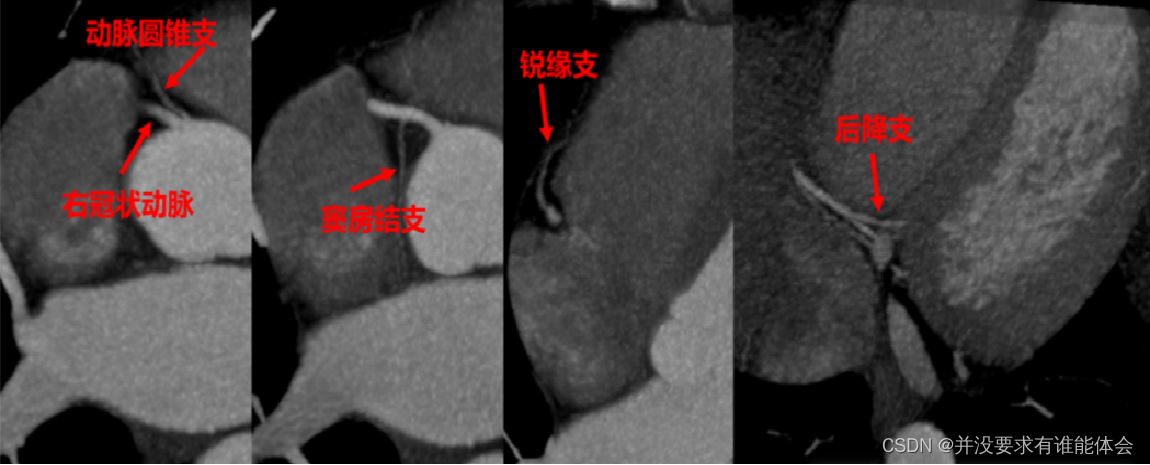

冠脉解剖-走形、分段

右冠状动脉:白右冠状赛发出后,行走于主肺动脉干和开主动脉根部间的右房室沟内,绕向心胜右后方再向左后走行,沿途发出圆锥支、实房结支、說缘支、后降支

圆锥支:第一分支,发自右冠状动脉最近端,供应右室的肺动脉圆锥。30%左右从主动脉发出;

实房结支:60%起自右冠状动脉,40%起自左冠状动脉;

税缘支:供应右心室前壁;

右后降支供应左心室下壁和房室结。

右冠分支